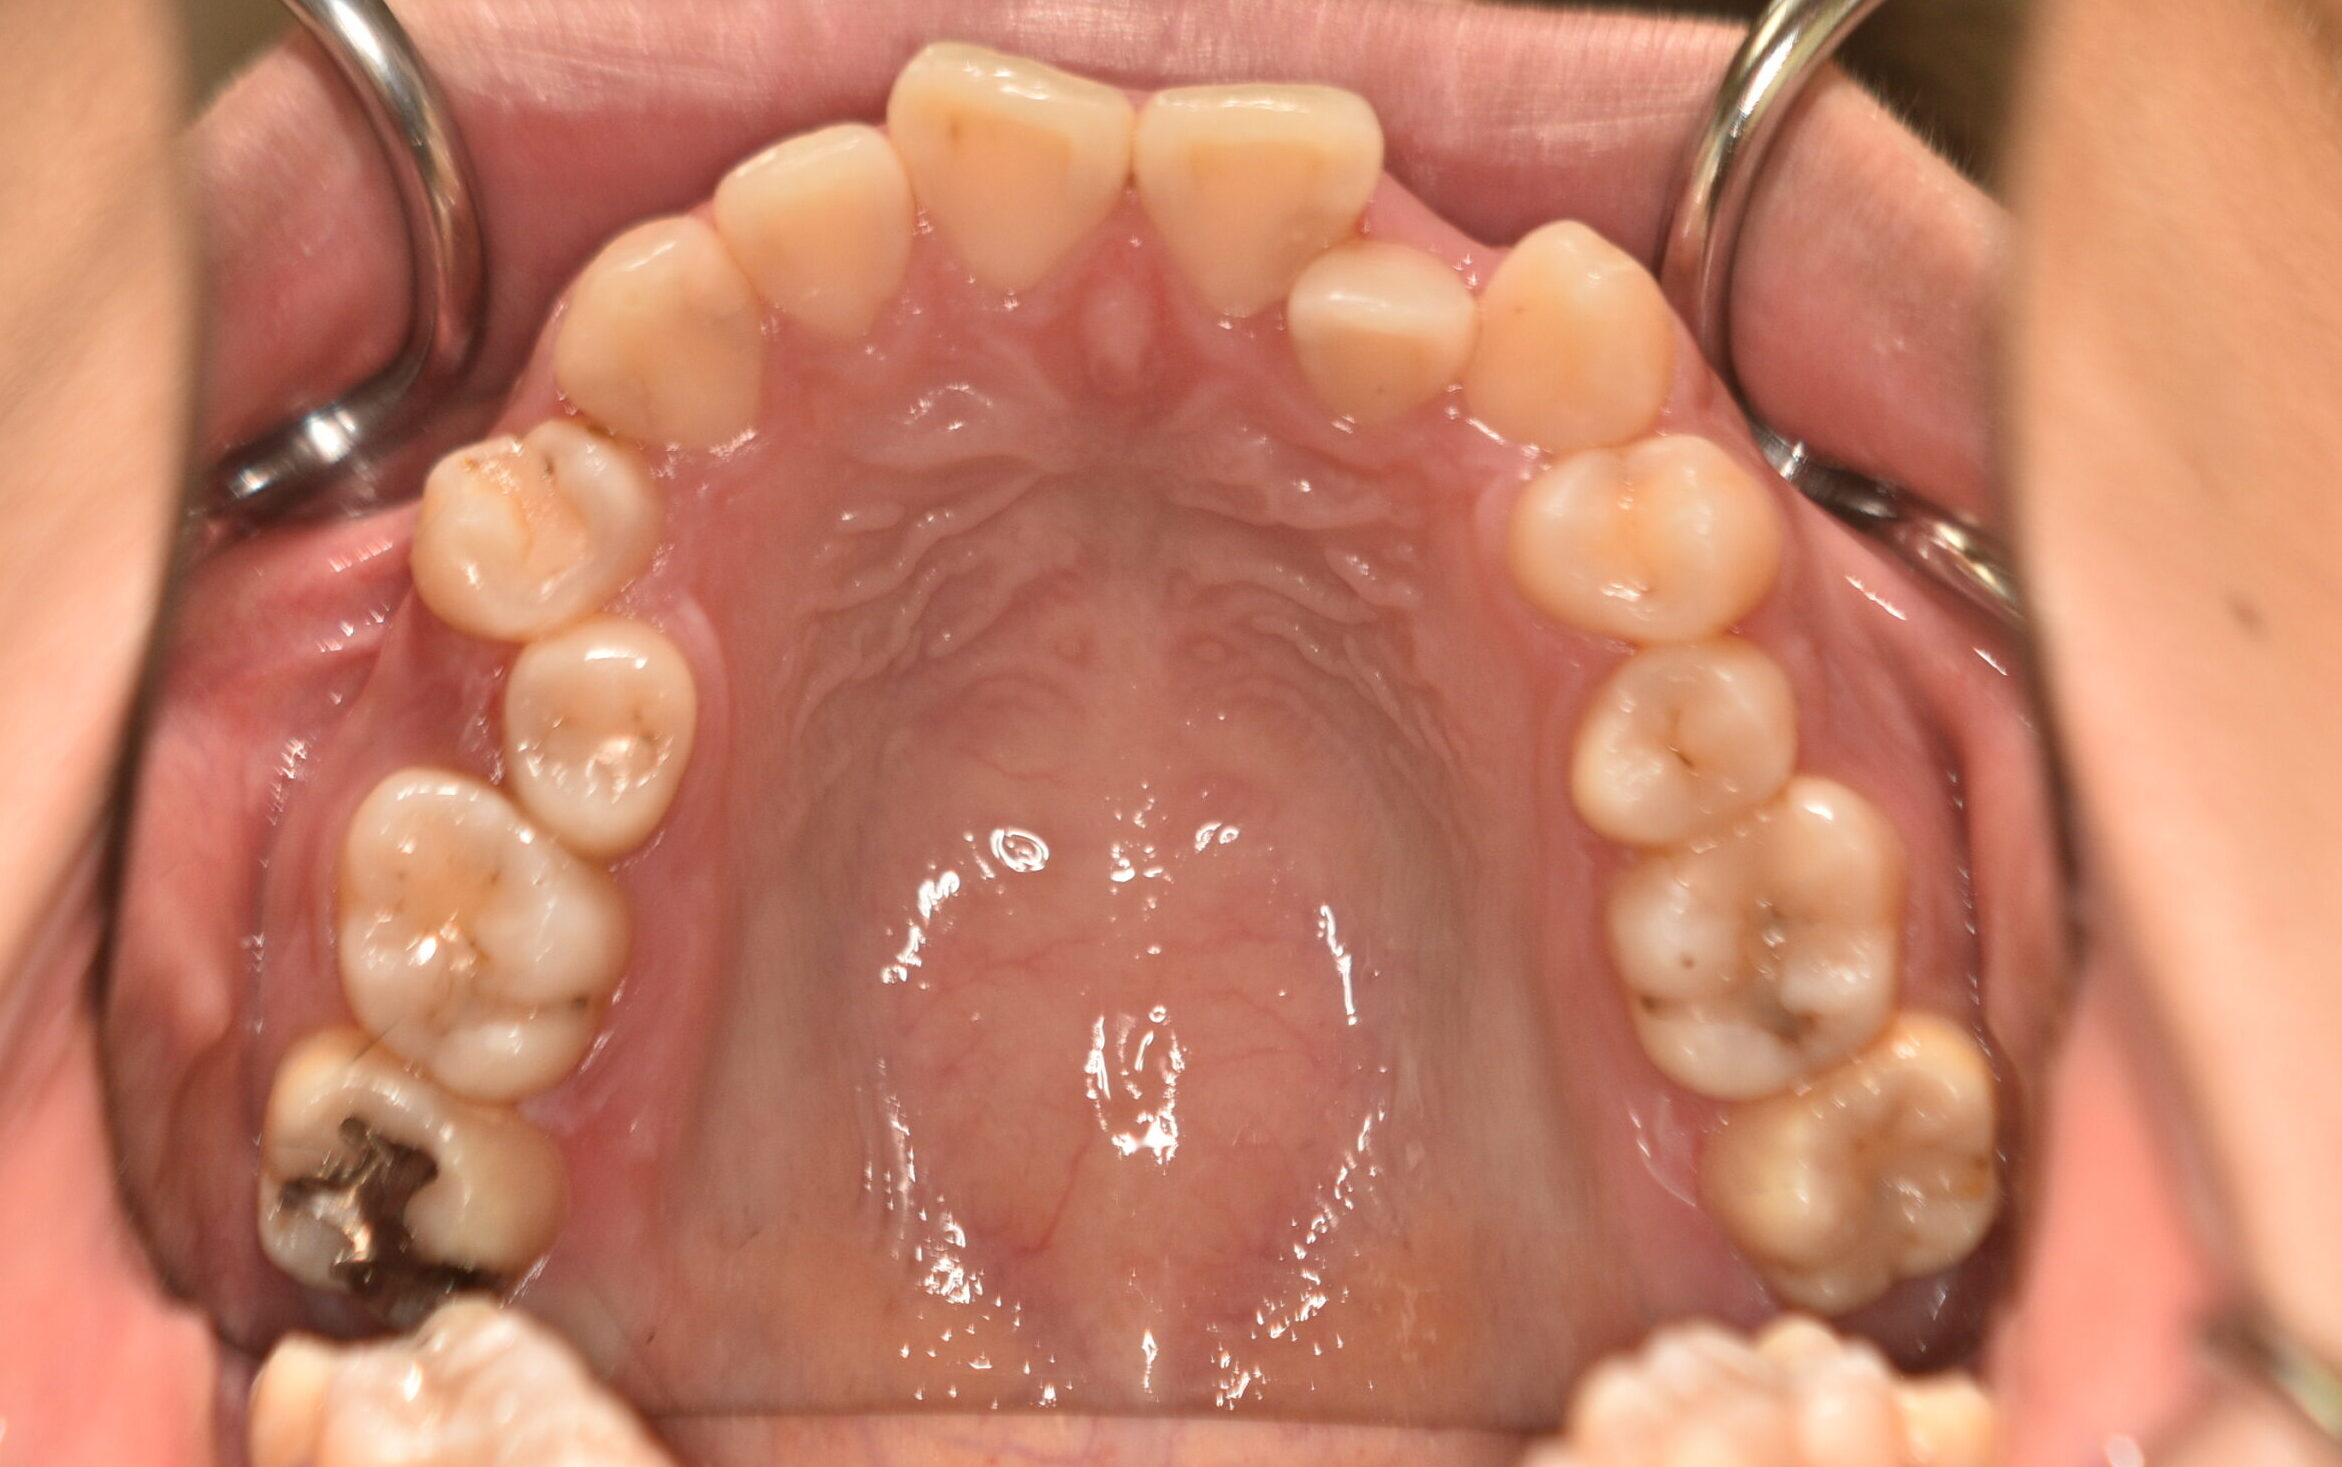

| 治療内容の詳細 | 初診時19歳の女性で、歯のがたつき、かみ合わせを気にされ来院されました。 検査の結果、上顎前歯部叢生を伴うアングルⅡ級1類不正咬合と診断しました。 治療としては、非抜歯の上、セルフライゲーション装置(デーモンシステム)で配列を行いました。 同時に顎間ゴムにて咬合関係の改善を行いました。 治療期間は、2年2ヶ月でした。 |